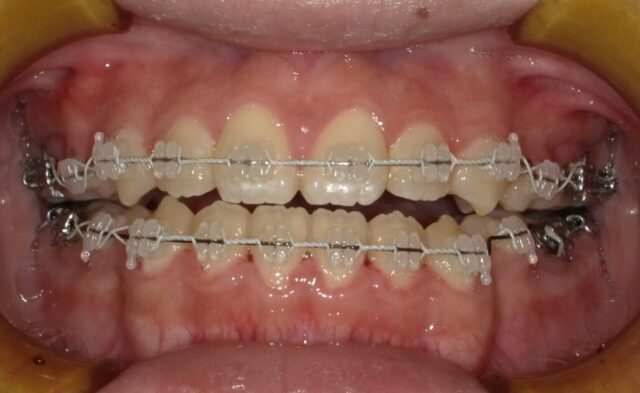

≪正面観≫

2023年5月

《動的治療期間1年8ヶ月》

before

after

| 診断名 | 上顎前歯部叢生を伴う下顎前突 開咬 |

| 治療方法・治療内容 | 1段階目:フェイシャルマスク 2段階目:ストレートワイヤーテクニック |